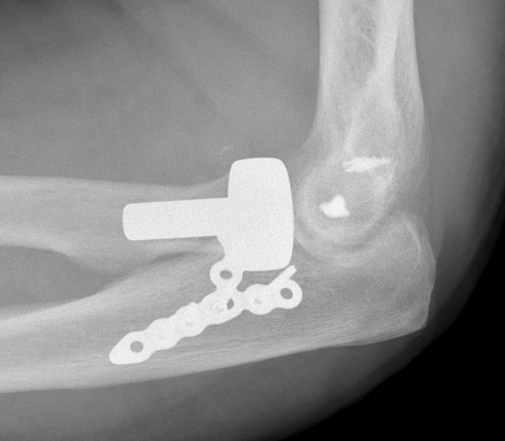

Radial head replacement with lag screw fixation of Type II coronoid